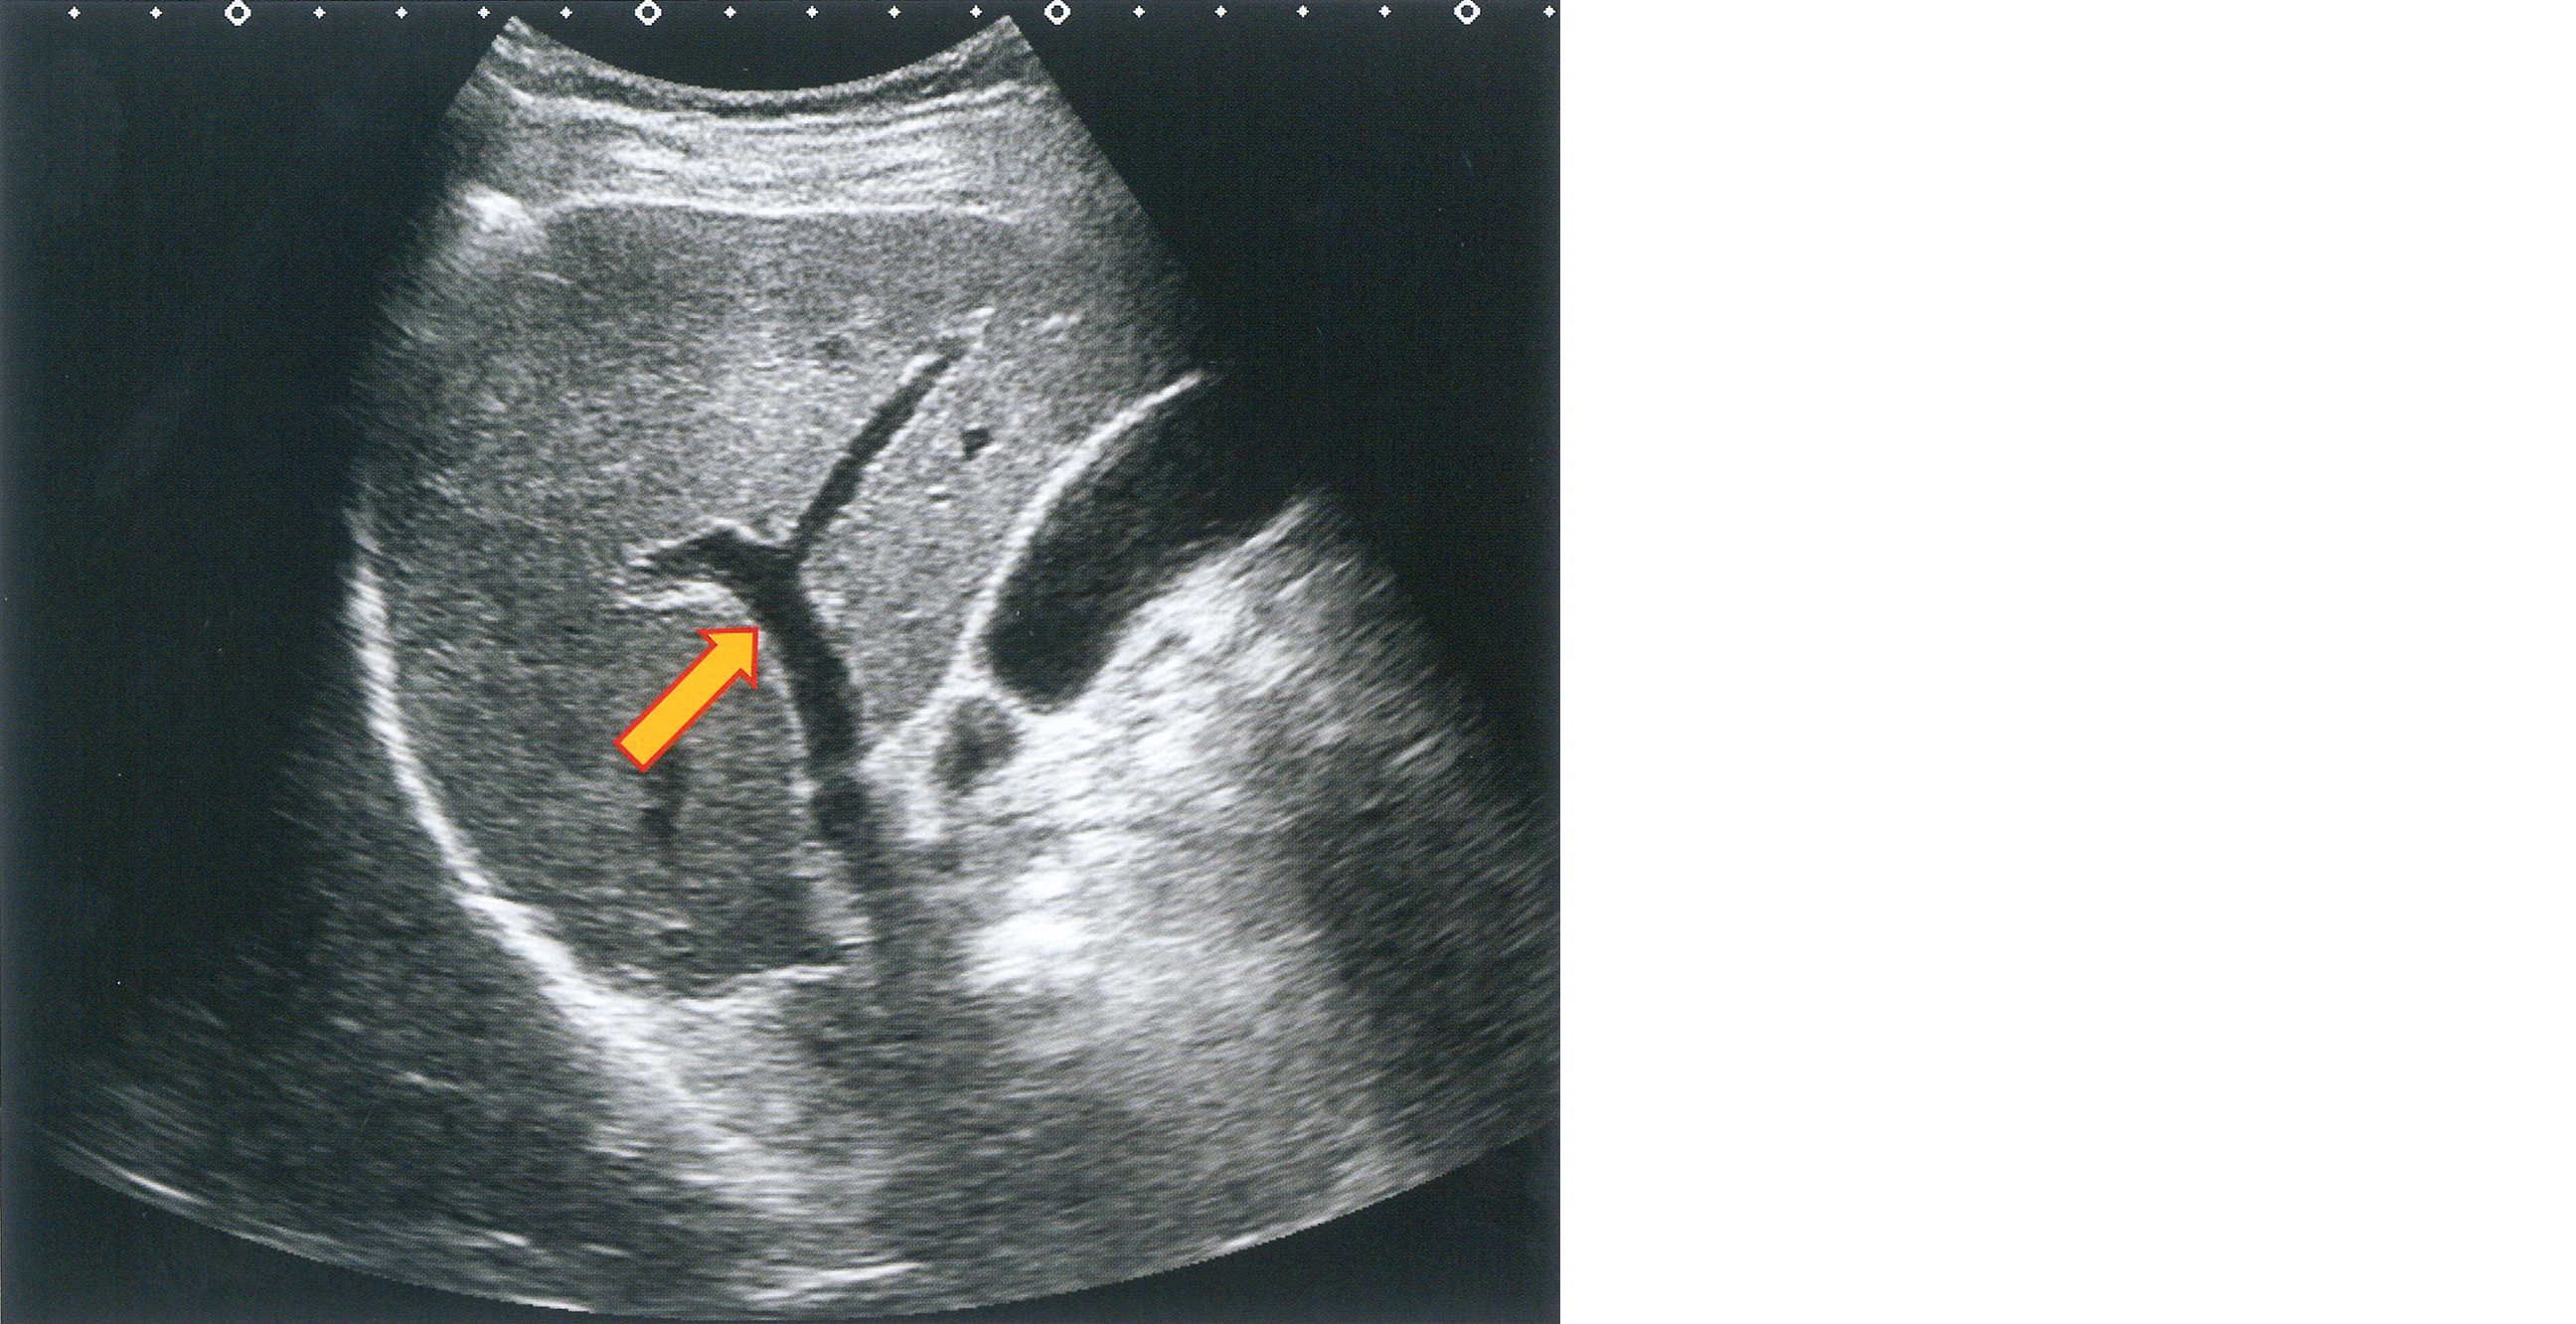

健常者の右肋間走査の超音波像を示す。

矢印で示すのはどれか。

• 1. 門 脈

• 2. 肝動脈

• 3. 左肝静脈

• 4. 中肝静脈

• 5. 右肝静脈